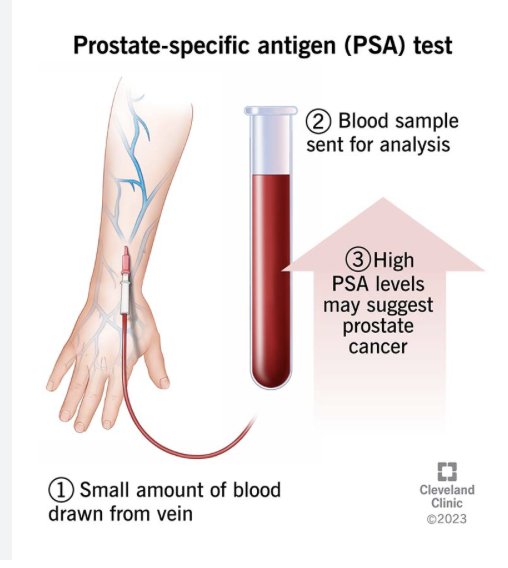

PSA

prostate specific antigen

Diagnostic lab test